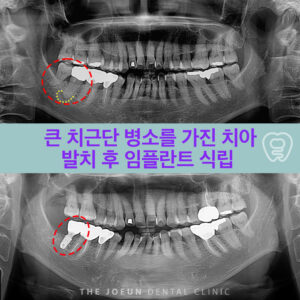

달서구임플란트잘하는곳 치조정 접근법을 통한 상악동 뼈이식술 임플란트는 치아가 빠진 부위에 티타늄으로 만들어진 인공치근을 치조골에 식립하여 상부에는 크라운을 제적하여 연결하는 보철치료르 말합니다. 치아의 뿌리부터 머리까지 자연치와 비슷한 모양으로 심미성이 뛰어나고, 자연치와 유사한 기능을 보이는데요. 이는 잇몸뼈에 식립체를 직접 식립하게 되는데 진행을 위해서는 치조골의 양과 상태가 충분해야 합니다. 치아를 상실했어도 치조골 상태가 더보기…